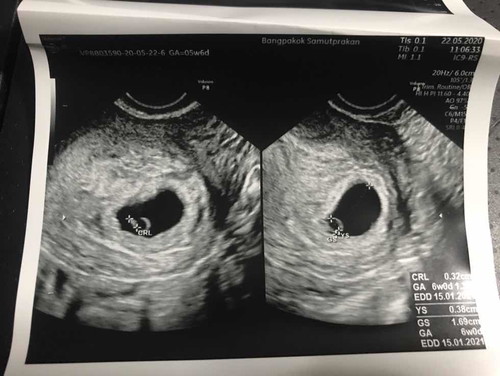

เราเพิ่งรู้ว่าตัวเองท้องได้6week ก่อนหน้านั้นเราทานไวน์ทุกวันเสาร์ ประมาณ1ขวด /เสาร์ มาโดยตลอด แถมได้รับสารเสพติดโดยบังเอิญอีกเนื่องจากเพื่อนใส่ยาอี ผสมลงในขวดไวน์ ซึ่งเราเพิ่งรู้เรื่อง ทำให้เรากังวลมาก ว่าจะมีผลต่อเด็กมั้ย ปรึกษาหมอมาเมื่อวาน หมอบอกตอนนี้ไม่สามารถบอกอะไรได้เพราะน้องยังเล็กเกินไปตรวจไม่ได้ จะตรวจได้ตอน5เดือน เรื่องยาถ้าไม่ได้ใช้ประจำหรือต่อเนื่องไม่น่ามีผลอะไร อาจทำให้น้องไฮเปอร์นิดๆ แต่เรื่องดื่มไวน์นั้น หมอบอกว่าเราดื่มเยอะอยู่เหมือนกัน ถ้าเรากังวลว่าน้องจะไม่สมบูรณ์อยากยุติให้ปรึกษารร.แพทย์ ศิริราช รามา จุฬา แต่ถ้าลองเสี่ยงก็ต้องรอน้อง5เดือน เราควรทำยังไง ถ้ารอ5เดือนแล้วไม่โอเค เราคงทำใจไม่ได้กว่านี้ แต่ถ้ายุติตอนนี้ แล้วน้องปกติดี ก็กลายเป็นว่าเราทำร้ายเค้า ตอนนี้เครียดมากค่ะ แถมการใช้ชีวิตก็นอนตี3-4 ตื่น9-10โมง บางวันก็นอนน้อย ทานอาหารก็เกือบบ่าย เราไม่ได้ทำสิ่งที่มีประโยชน์กับลูกเลย เราควรทำไงต่อคะ สับสน ร้องไห้ตลอดเลยค่ะ